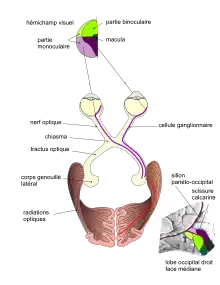

Le système visuel humain est l'ensemble des organes participant à la perception visuelle humaine, de la rétine au système sensori-moteur. Son rôle est de percevoir et d'interpréter deux images en deux dimensions en une image en trois dimensions. Il est principalement constitué de l'œil (et plus particulièrement la rétine), des nerfs optiques, du chiasma optique, du tractus optique, du corps genouillé latéral, des radiations optiques et du cortex visuel.

(P1) le renversement de l'image par le système optique de l’œil dans le sens haut/bas et gauche/droite

(P2) au niveau du chiasma, le croisement des fibres issues de l'hémirétine nasale et la projection du même côté des fibres issues de l'hémirétine temporale

(P3) au niveau des radiations optiques, les fibres représentant le quadrant supérieur arrivent sur la lèvre inférieure de la scissure calcarine (et inversement)

(P4) la fovéa, au centre du champ visuel, se projette dans la partie postérieure du cortex strié. La partie binoculaire de chaque hémichamp visuel se projette dans la région intermédiaire du cortex strié. La partie temporale, monoculaire de chaque champ visuel se projette sur la partie antérieure du cortex visuel.

Les nerfs optiques de chaque œil se rejoignent au niveau du chiasma optique, ce qui permet de redistribuer l'information visuelle selon qu'elle est dans la partie droite ou dans la partie gauche du champ visuel (chaque œil voit à gauche et à droite en même temps). L'hémichamp gauche va dans l'hémisphère droit et vice-versa (il y a une inversion).

La continuation des nerfs optiques après le chiasma s'appelle le tractus optique (en). Dans chaque hémisphère, il distribue l'information visuelle à différents noyaux :